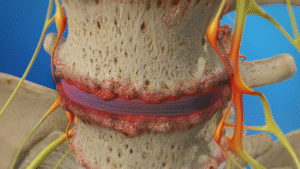

- Minimally invasive procedures

Back pain

Il dolore lombare è una condizione molto frequente. Può avere diverse cause, come problemi muscolari, articolari o discali, e spesso limita le attività quotidiane.